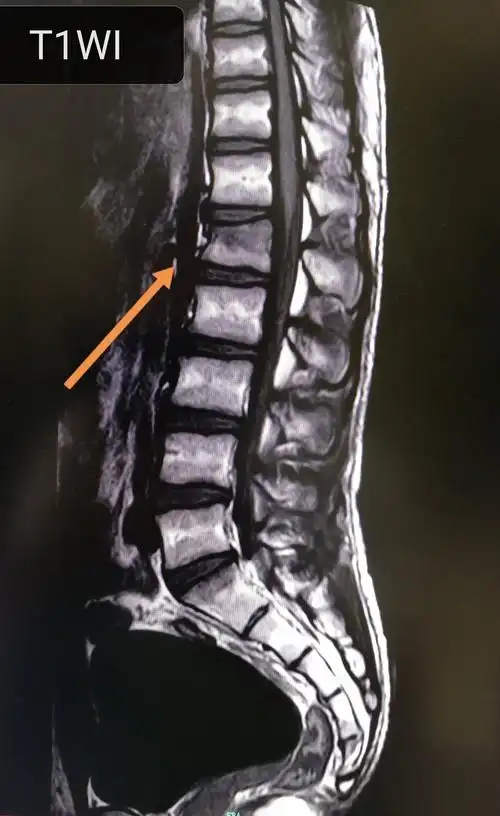

44岁腰椎3,4椎体压缩性骨折椎体成型手术一例